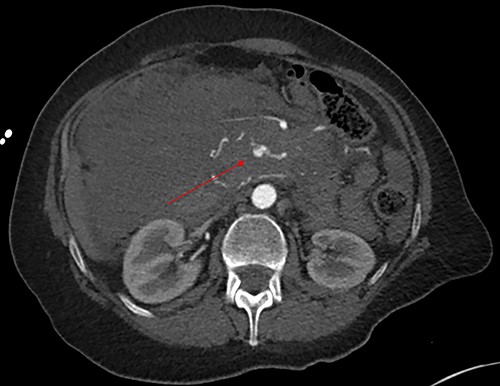

Initially, the main diagnosis considered was an aortic dissection. Other initial general surgical differentials were a perforated viscous or severe pancreatitis. Computed tomography (CT) angiogram showed a 6 mm pseudoaneurysm arising from a branch vessel 3 cm distal to the origin of the SMA. There was no active arterial blush; however, there was a large associated mesenteric haematoma (measuring 4.5 × 8.0 × 13 cm) with large volume haemoperitoneum (Figs 1–3). There was also a splenic artery aneurysm measuring 5 mm with no evidence of active haemorrhage. After the CT scan, she was noted to be haemodynamically unstable when lying supine, due to inferior vena cava compression by the mesenteric haematoma. A pillow was placed under her left lateral side to act as a wedge to reduce this. She proceeded to urgent angioembolization by interventional radiology, which confirmed the pseudoaneurysm on angiography (Fig. 4, left). The SMA was accessed and the aneurysm was successfully embolized with 3 mm diameter 15 cm length Ruby micro-soft detachable coil (Fig. 4, right).

Axial image of the large retroperitoneal haematoma in portal venous phase.